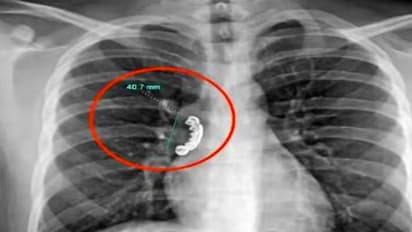

आन-फानन में युवक को अस्पताल ले जाया गया। जहां डॉक्टरों ने उसका एक्सरे किया। डॉक्टर उसका एक्सरे देख कर दंग रह गए।उसके गले में काफी अंदर जाकर डेन्चर फंसा गया था। इसके बाद डॉक्टरों ने एक लचीली ट्यूब डालकर उसे निकालने की कोशिश हुई तो वह और भी अंदर चला गया। बाद में ऑपरेशन करके डेन्चर को बाहर निकाला गया। तब जाकर इस शख्स की जान बच पाई।

डॉक्टरों ने बताया कि अगर उसे अस्पताल लाने में कुछ और देर हो जाती तो उसकी दम घुटने की वजह से मौत तक हो सकती थी।क्योंकि डेन्चर फंसने की वजह से उसकी सांस बिल्कुल भी अंदर बाहर नहीं हो रही थी। फेफड़े के वायुमार्ग की मांसपेशियां टाइट हो गई थीं।